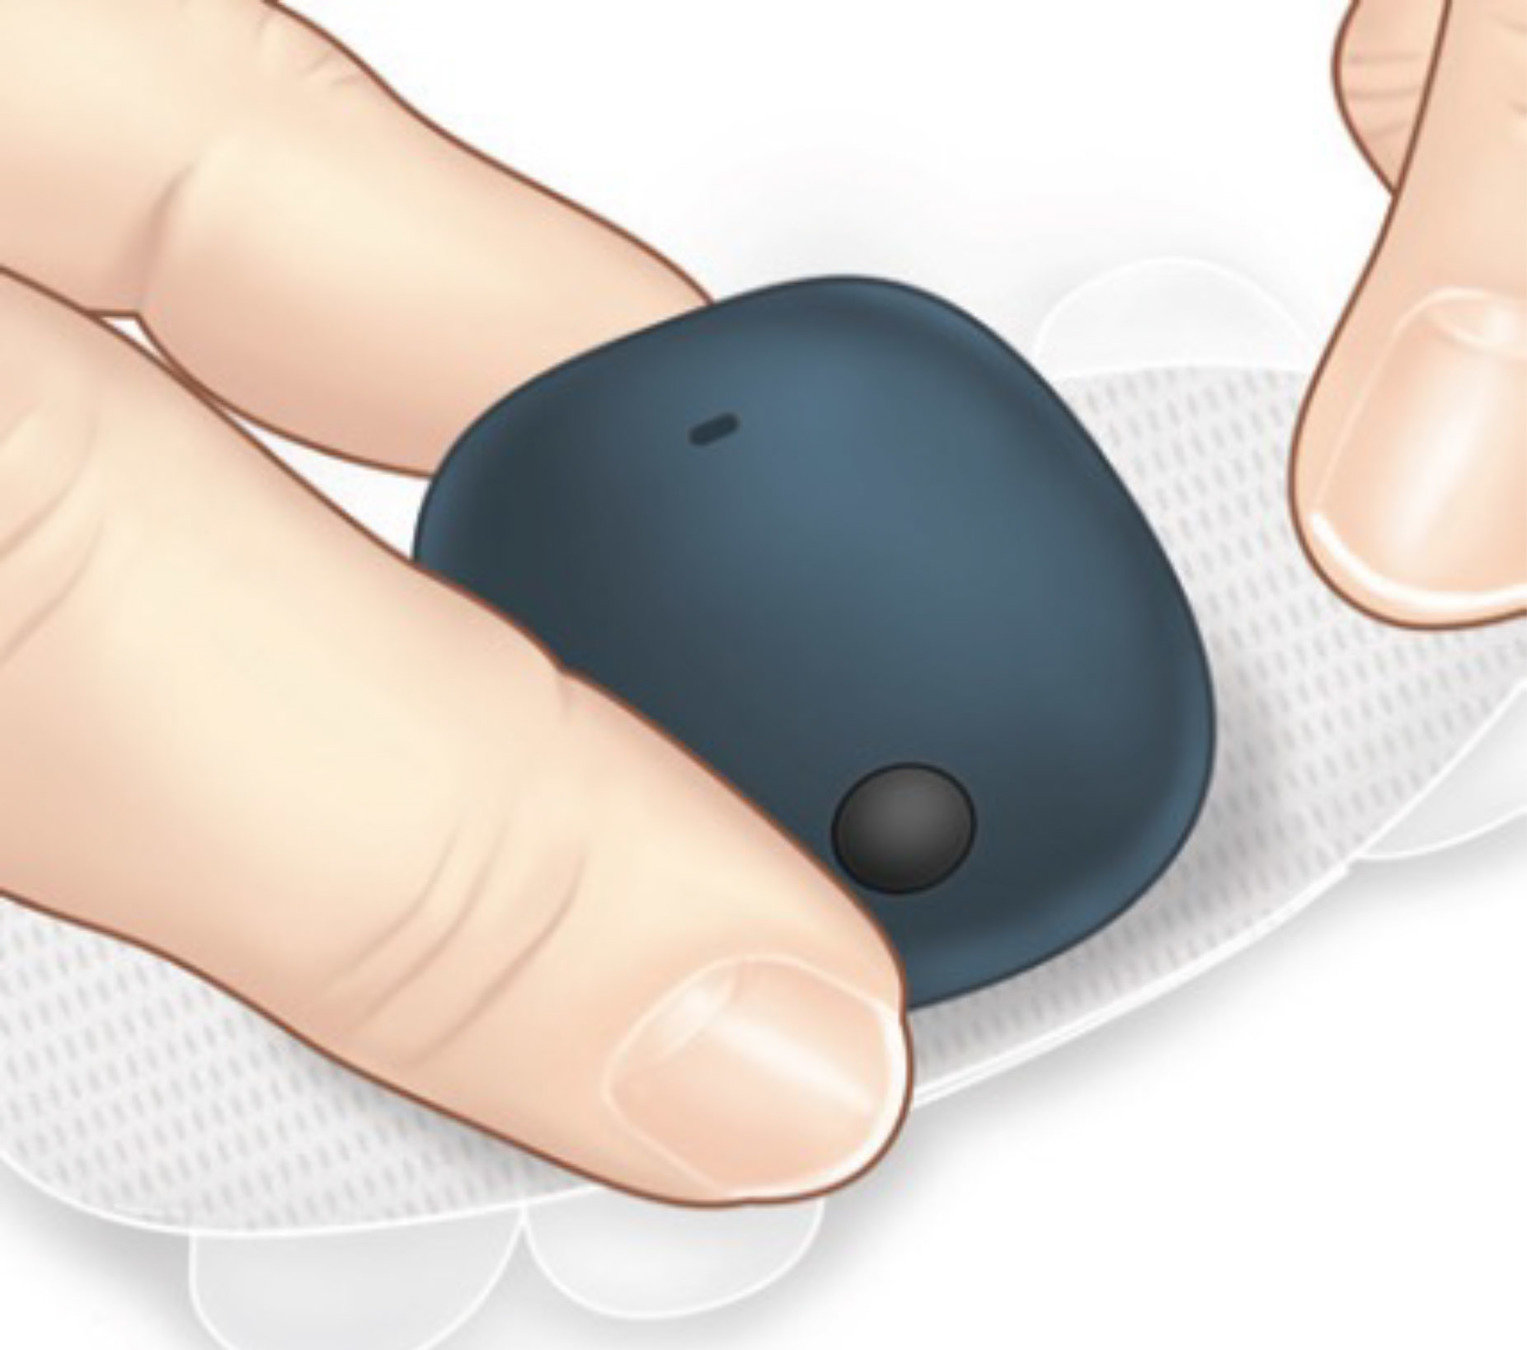

Los pasos para encender o apagar el transmisor inteligente Eversense® E3 son los mismos.

Mantenga pulsado el botón de encendido durante unos 5 segundos hasta que el transmisor inteligente vibre. A continuación, suelte el botón de encendido y observe el indicador LED.

Si parpadea en color verde, está encendido.

Si parpadea en color naranja, está apagado.

y ponga el transmisor inteligente en el modo detectable pulsando firmemente el botón de encendido tres veces hasta que el indicador LED parpadee alternando los colores verde y naranja.